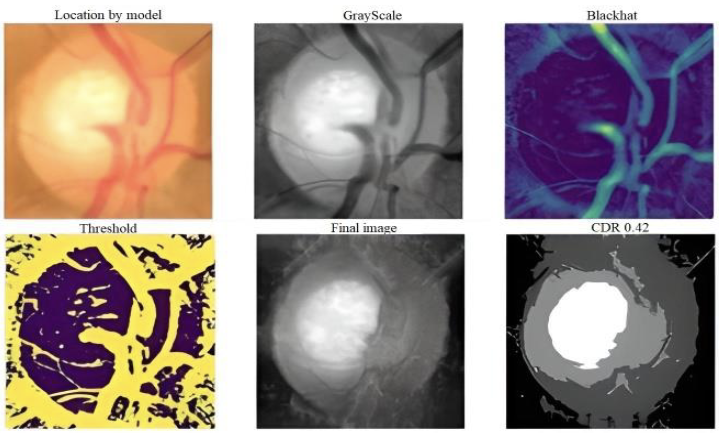

Glaucoma is a leading cause of irreversible blindness worldwide, affecting millions of people. Early diagnosis is essential to reduce visual loss, and various techniques are used for glaucoma detection. In this work, a hybrid method for glaucoma fundus image localization using pre-trained Region-based Convolutional Neural Networks (R-CNN) ResNet-50 and cup-to-disk area segmentation is proposed. The ACRIMA and ORIGA databases were used to evaluate the proposed approach. The results showed an average confidence of 0.879 for the ResNet-50 model, indicating it as a reliable alternative for glaucoma detection. Moreover, the cup-to-disc ratio was calculated using Gradient-color-based optic disc segmentation, coinciding with the ResNet-50 results in 80% of cases, having an average confidence score of 0.84. The approach suggested in this study can determine if glaucoma is present or not, with a final accuracy of 95% with specific criteria provided to guide the specialist for an accurate diagnosis. In summary, the proposed model provides a reliable and secure method for diagnosing glaucoma using fundus images.